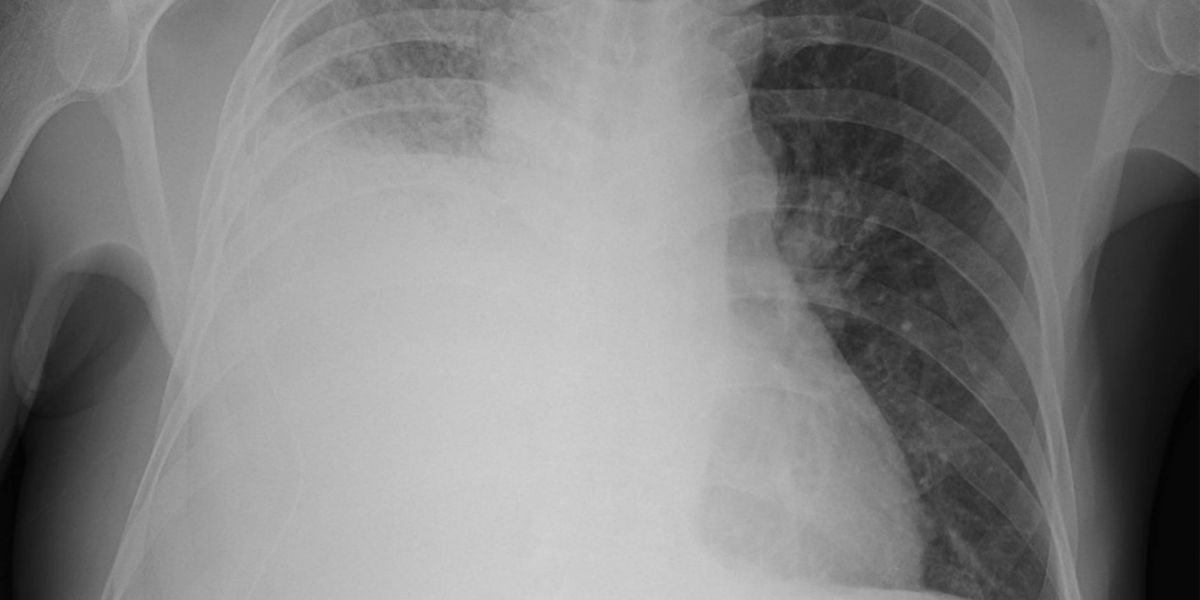

Pleural effusion occurs when excess fluid collects in the pleural space, the thin gap between the lungs and the chest wall. Under normal conditions, only a few teaspoons of fluid are present. This small amount acts as lubrication, preventing friction as the lungs expand.

When the balance between fluid production and drainage is disrupted, fluid begins to accumulate. As it increases, the lungs may not fully expand. This can lead to shortness of breath, chest discomfort, and decreased oxygen levels. Doctors often categorize pleural effusion into two main types: transudative and exudative. This distinction helps determine the underlying cause.